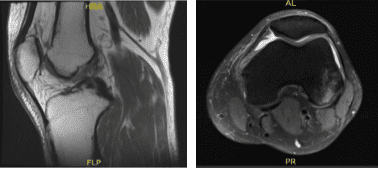

Resonancia magnética – 3T rodilla izquierda sin contraste

Hoy se ha presentado el resultado de la resonancia magnética y ha mostrado un desgarro complejo del cuerno posterior del menisco medial, una pequeña escisión, una pequeña clivación horizontal del cuerpo del menisco lateral, una lesión por impacto en la parte posterior no portante del cóndilo femoral lateral con fractura pequeña,

Lesión del ligamento colateral medial grado 2 con desgarro longitudinal vertical, contusión en la parte inferior medial de la rótula, derrame articular moderado con sinovitis.